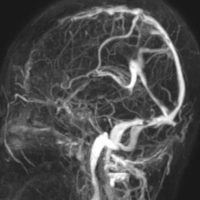

全髄膜の腫瘍化,NF-2

テント下を含めて頭蓋内の全ての髄膜が同時に腫瘍化してきます。この患者さんはNF-2なのですが,NF-2がない患者さんにもmeningiomatosisはあります。脳圧亢進による視神経乳頭萎縮で両側の視力が無くなるというような症状が出ます。これは手術適応がないタイプです。